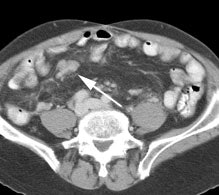

Initial staging for extrahepatic metastases: The patient below underwent FDG PET imaging to assess for extrahepatic metastatic disease prior to definitive surgical intervention. The PET exam demonstrates uptake within two hepatic metastases (black arrows on PET scan and yellow arrows on CT images) and in the patients primary colon cancer (blue arrow on PET scan and white arrow on CT image). No other sites of abnormal tracer uptake were identified which supports surgical intervention in this case. |

Initial staging for colorectal carcinoma: The patient below presented for evaluation of colorectal carcinoma. The CT scan demonstrated a large liver mass (red arrows) compatible with metastatic disease. The patient's cecal mass (black arrow on PET scan) was not detected on the CT study (white arrow). No other lesions were identified on the PET scan. |